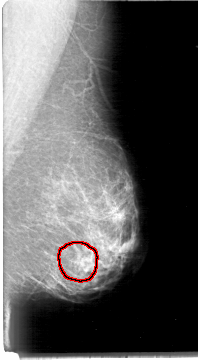

FILE: D_4004_1.LEFT_CC.OVERLAY

TOTAL_ABNORMALITIES 1

ABNORMALITY 1

LESION_TYPE MASS SHAPE OVAL MARGINS OBSCURED

ASSESSMENT 0

SUBTLETY 3

PATHOLOGY BENIGN

TOTAL_OUTLINES 1

BOUNDARY

LEFT_CC LINES 5386 PIXELS_PER_LINE 3031 BITS_PER_PIXEL 12 RESOLUTION 43.5 OVERLAY